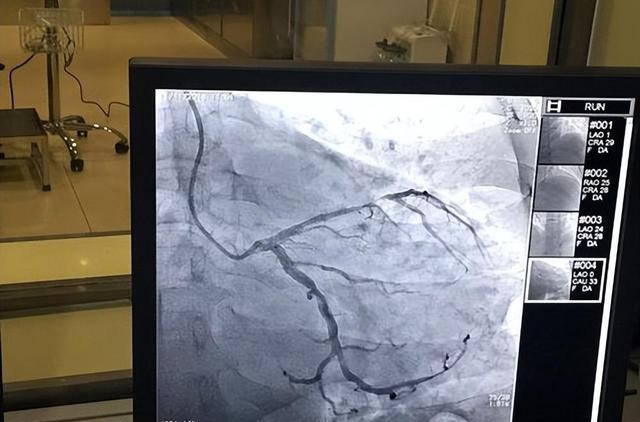

一、心脏造影

心脏造影主要是看心脏的管道 , 也就是看有没有斑块 , 有没有狭窄 , 当心脏动脉血管的狭窄超过50%了 , 叫冠心病 。 所以就算是做个造影 , 也只能看有没有冠心病 , 而不是所有 。

心脏造影可能会发生造影剂过敏 , 穿刺出血 , 血肿 , 夹层 , 血管损伤 , 甚至导致室颤 , 危及生命 。

所以心脏造影不是一项常规检查 , 必须严格把握适应症 。